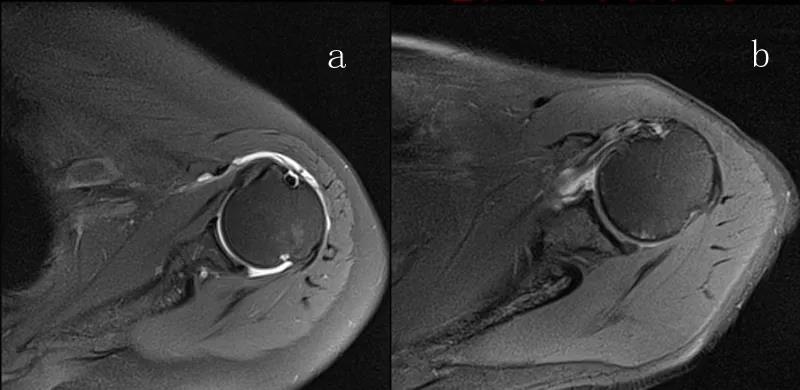

图21 斜冠状位(临床常用)a.T2,b.T1

图22 斜矢状位 a.冈上肌出口,肩袖诊断不如斜冠状位;b.冈上肌及肌腹脂肪浸润成度,评估手术与否

图23 横断位a.正常肩胛下肌;b.肩胛下肌损伤